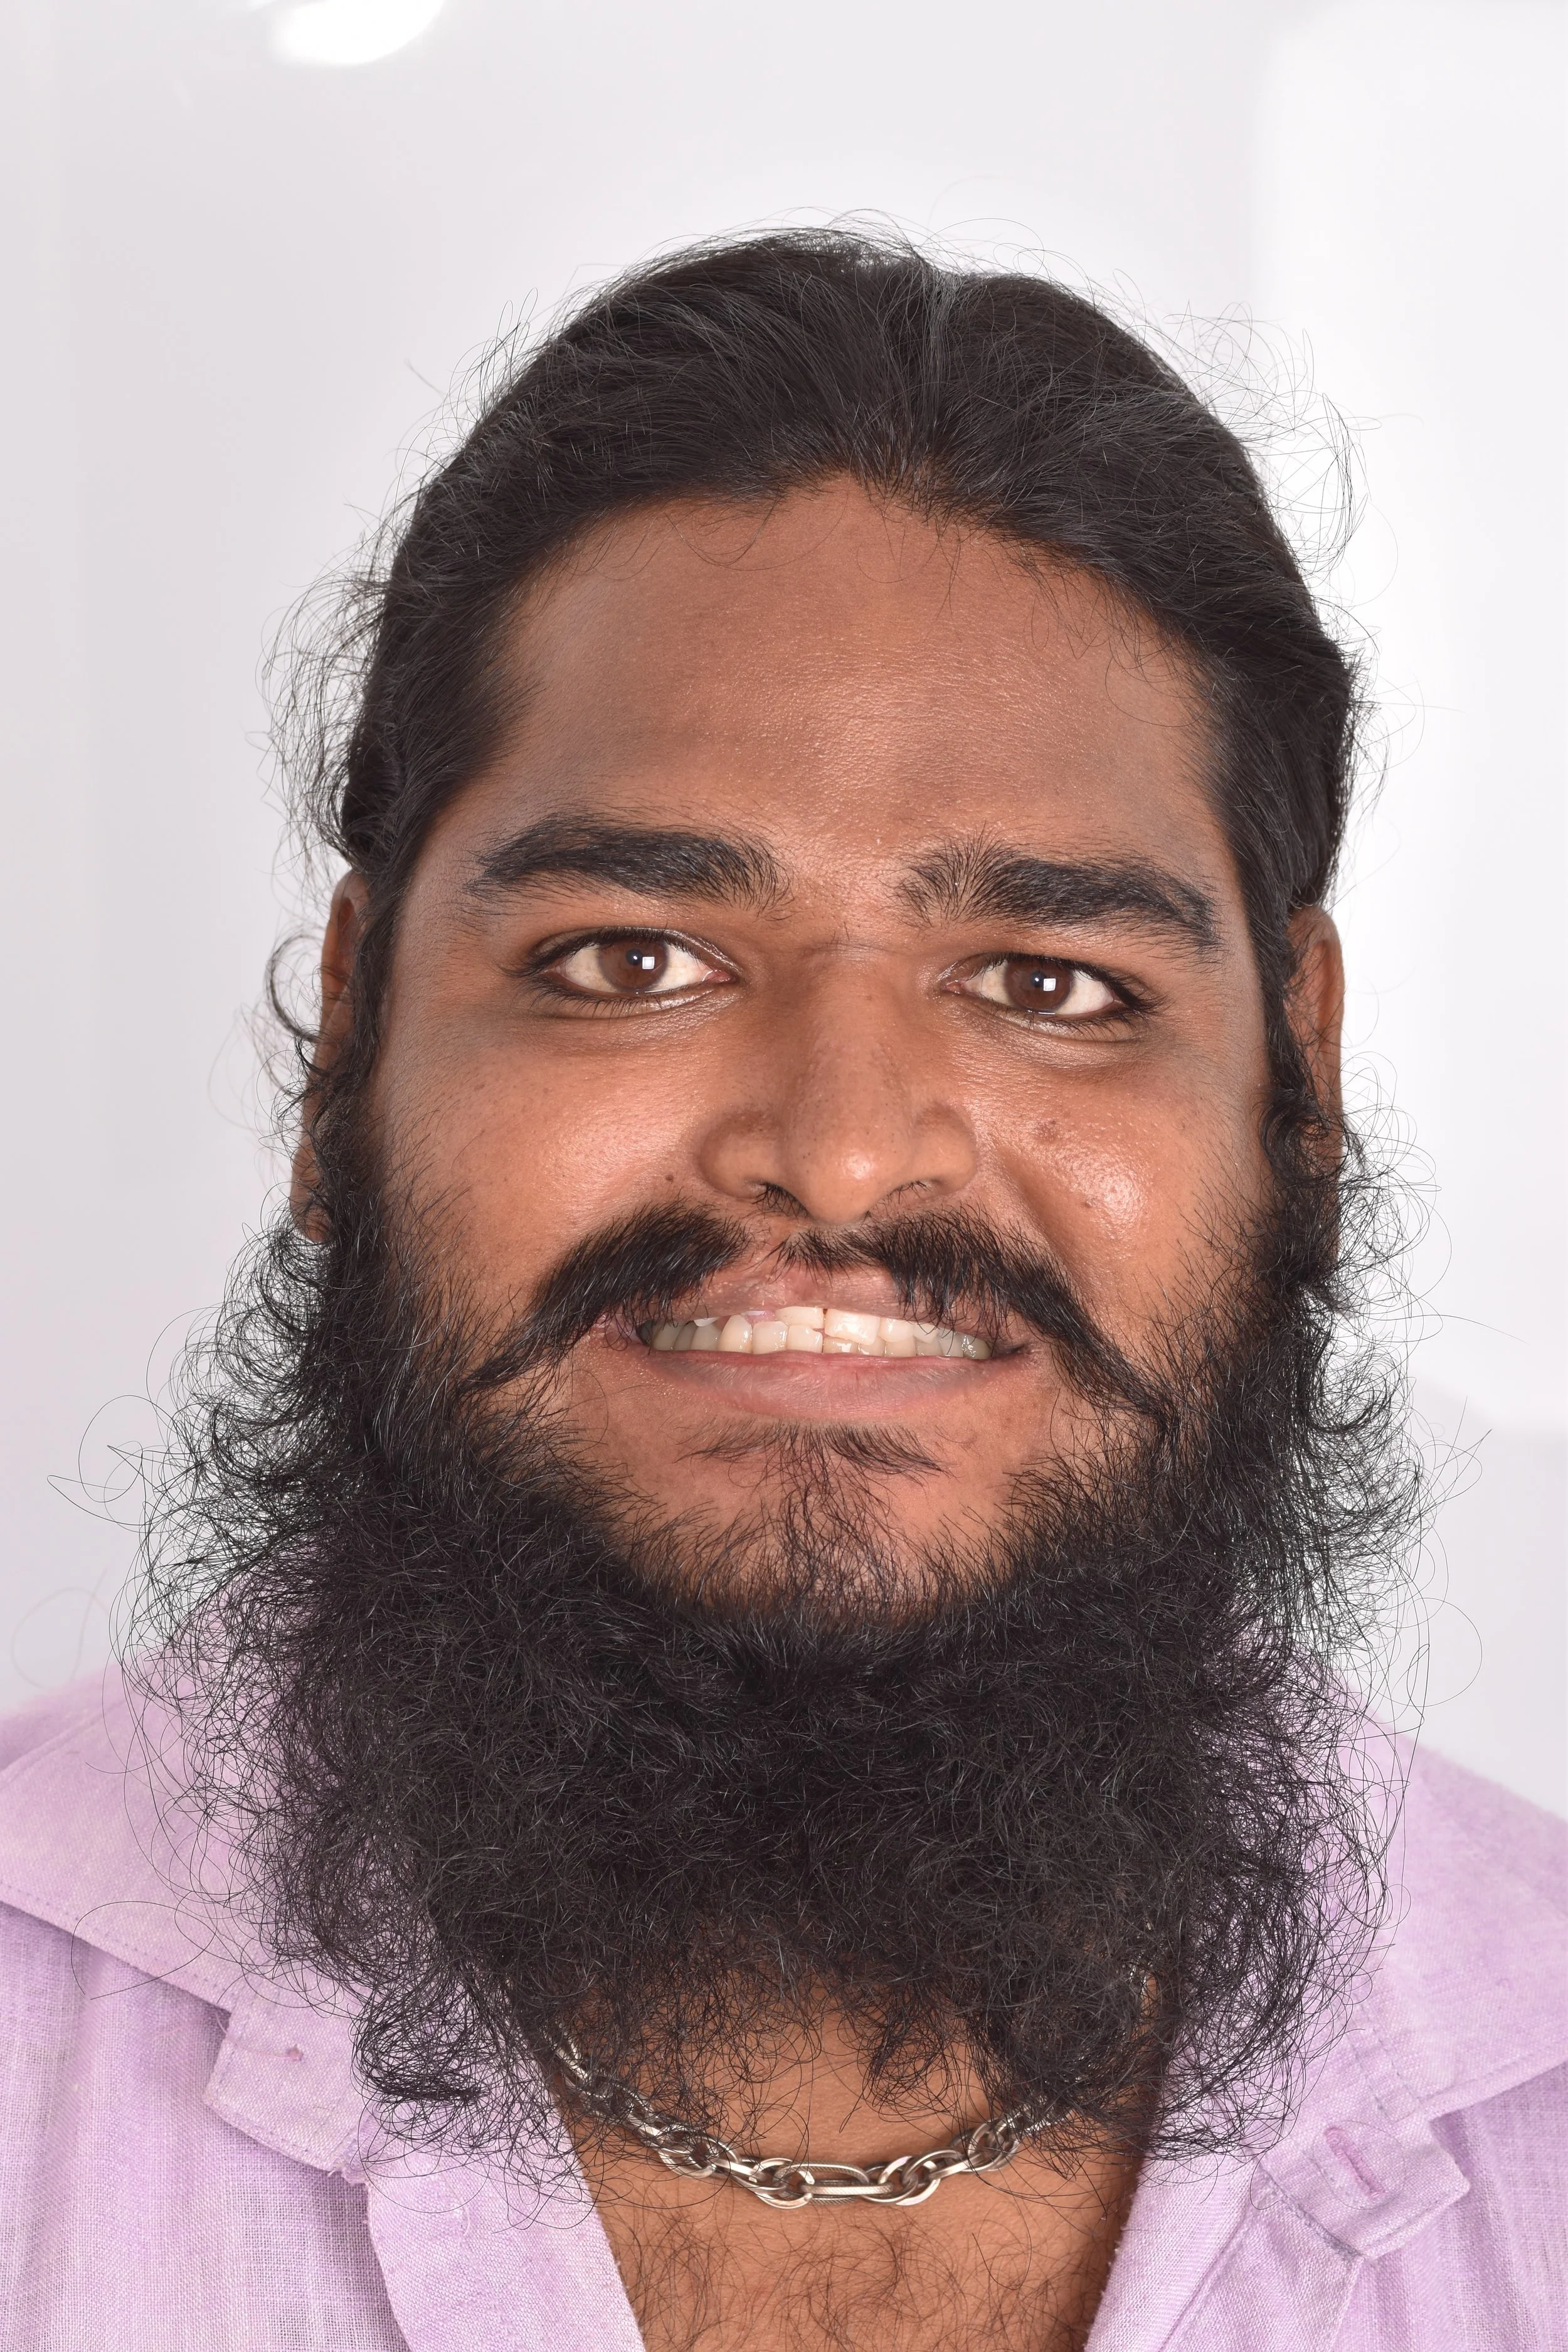

DISTALIZATION OF ENTIRE DENTITION WITH MINI-SCREWS ASSISSTED BY ESTHETIC SMILE MAKEOVER

DISTALIZATION OF ENTIRE DENTITION WITH MINI-SCREWS ASSISSTED BY ESTHETIC SMILE MAKEOVER